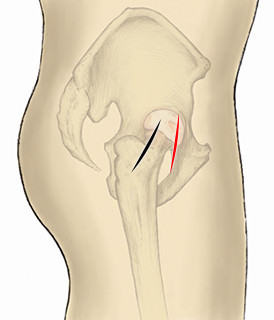

前外側進入法(ALS)は黒で明示。前方進入法(DAA)は赤で明示